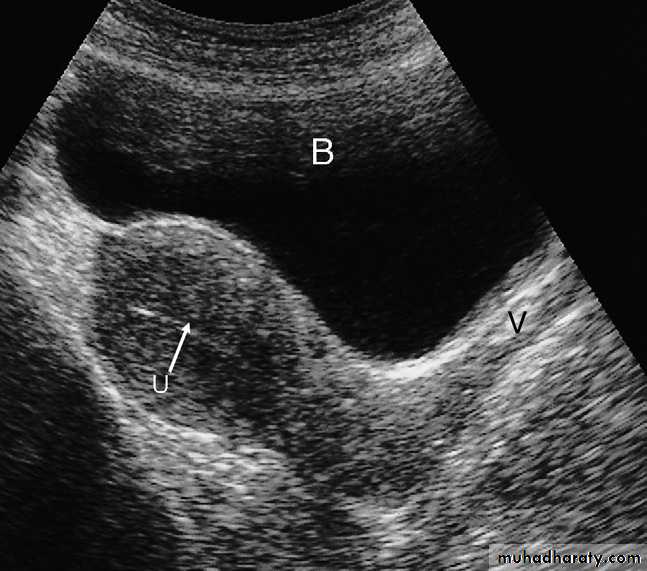

UltrasoundUltrasound of the pelvis can be carried out in two ways:

- Scanning trans abdominal wall (usually with full bladder ).

- Trans vaginally with a specialized ultrasound probe inserted in the vagina ( examination done with empty bladder) image quality is much better than the trans abdominal technique .

On a midline longitudinal or transverse scan

- The vagina can be recognized as a tubular structure, with a central linear echo arising from the opposing vaginal surfaces.

- The uterus lies immediately behind the bladder, and the body of the uterus can be seen to be in continuity with the cervix and vagina.

The myometrium shows low level echoes, whereas the endometrial cavity gives an echogenic linear stripe.